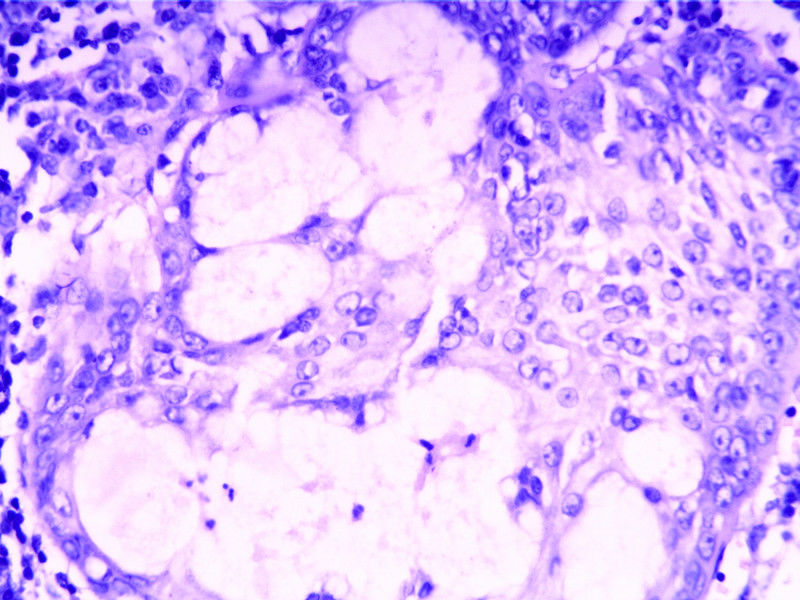

要想Hold住这个肿物的病理诊断,需要了解:

需要鉴别的肿瘤:

(1)皮脂腺淋巴腺瘤

(2)伴有淋巴组织间质的皮脂腺癌(皮脂腺淋巴腺癌)

(3)良性淋巴上皮病

(4)粘膜相关淋巴组织淋巴瘤(MALT淋巴瘤)

(5)转移性粘液表皮样癌